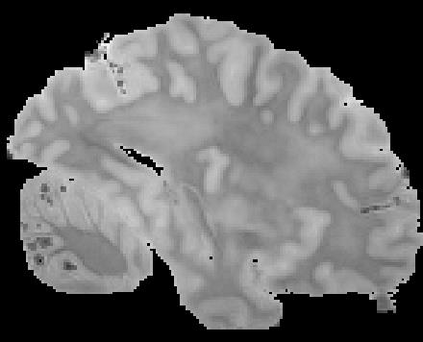

In neuroimaging, MRI tissue properties characterize underlying neurobiology, provide quantitative biomarkers for neurological disease detection and analysis, and can be used to synthesize arbitrary MRI contrasts. Estimating tissue properties from a single scan session using a protocol available on all clinical scanners promises to reduce scan time and cost, enable quantitative analysis in routine clinical scans and provide scan-independent biomarkers of disease. However, existing tissue properties estimation methods - most often $\mathbf{T_1}$ relaxation, $\mathbf{T_2^*}$ relaxation, and proton density ($\mathbf{PD}$) - require data from multiple scan sessions and cannot estimate all properties from a single clinically available MRI protocol such as the multiecho MRI scan. In addition, the widespread use of non-standard acquisition parameters across clinical imaging sites require estimation methods that can generalize across varying scanner parameters. However, existing learning methods are acquisition protocol specific and cannot estimate from heterogenous clinical data from different imaging sites. In this work we propose an unsupervised deep-learning strategy that employs MRI physics to estimate all three tissue properties from a single multiecho MRI scan session, and generalizes across varying acquisition parameters. The proposed strategy optimizes accurate synthesis of new MRI contrasts from estimated latent tissue properties, enabling unsupervised training, we also employ random acquisition parameters during training to achieve acquisition generalization. We provide the first demonstration of estimating all tissue properties from a single multiecho scan session. We demonstrate improved accuracy and generalizability for tissue property estimation and MRI synthesis.